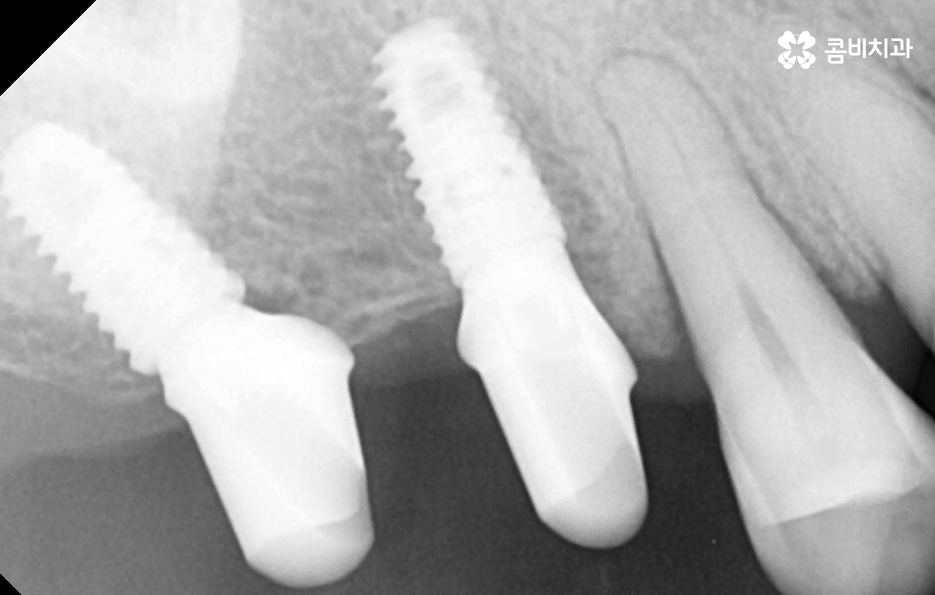

임플란트의 원리 자체는 어떤 치료에도 비슷하게 적용되지만 치료 계획을 세우다보면 치아를 상실한 원인도 다르고 현재 잇몸 상태부터 전신 건강의 차이가 있기 때문에 세부적인 치료 계획이 달라지면서 임플란트의 치료 방법은 다양하게 적용되고 있는데요

예를 들어 20대에 충치로 치아 하나를 발치하게 된 사례와 60대 이후 노인분이 풍치로 인해 대부분의 치아를 잃고 전체임플란트를 해야 한다면 임플란트의 치료 원리 자체는 비슷해도 치료 계획은 전혀 달라지는 것과 비슷한 이치라고 볼 거예요